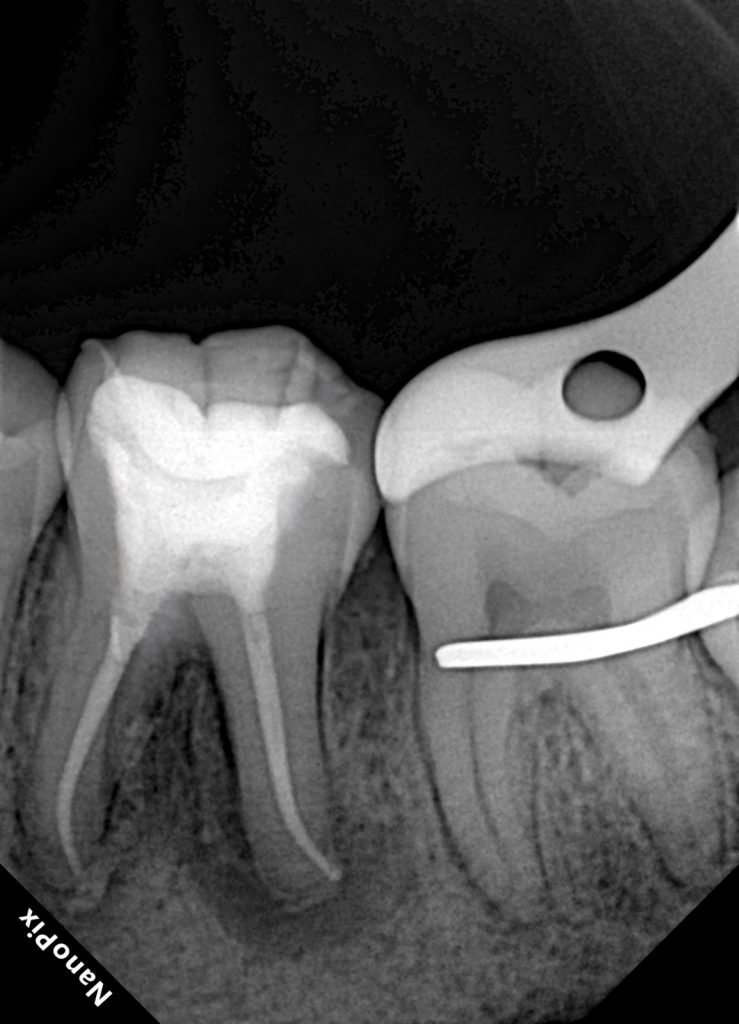

Clinical examination revealed a deeply carious mandibular first molar associated with pulpal pathology. Percussion sensitivity and radiographic findings confirmed the need for root canal treatment. The tooth exhibited weakened cusps due to caries and access requirements.

Conservative access preparation was performed with attention to maintaining pericervical dentin. The canal system was identified and negotiated systematically. Working lengths were established, and patency was confirmed.

Following complete drying of the canals, obturation was performed to achieve a dense, three-dimensional seal. Special care was taken to ensure proper adaptation in the apical and coronal thirds.

A definitive coronal seal was placed immediately after obturation to prevent microleakage.

Mandibular first molars are exposed to significant occlusal forces, making them highly susceptible to post-endodontic fracture if restored inadequately. Evidence consistently supports cuspal coverage for endodontically treated posterior teeth to reduce fracture risk.